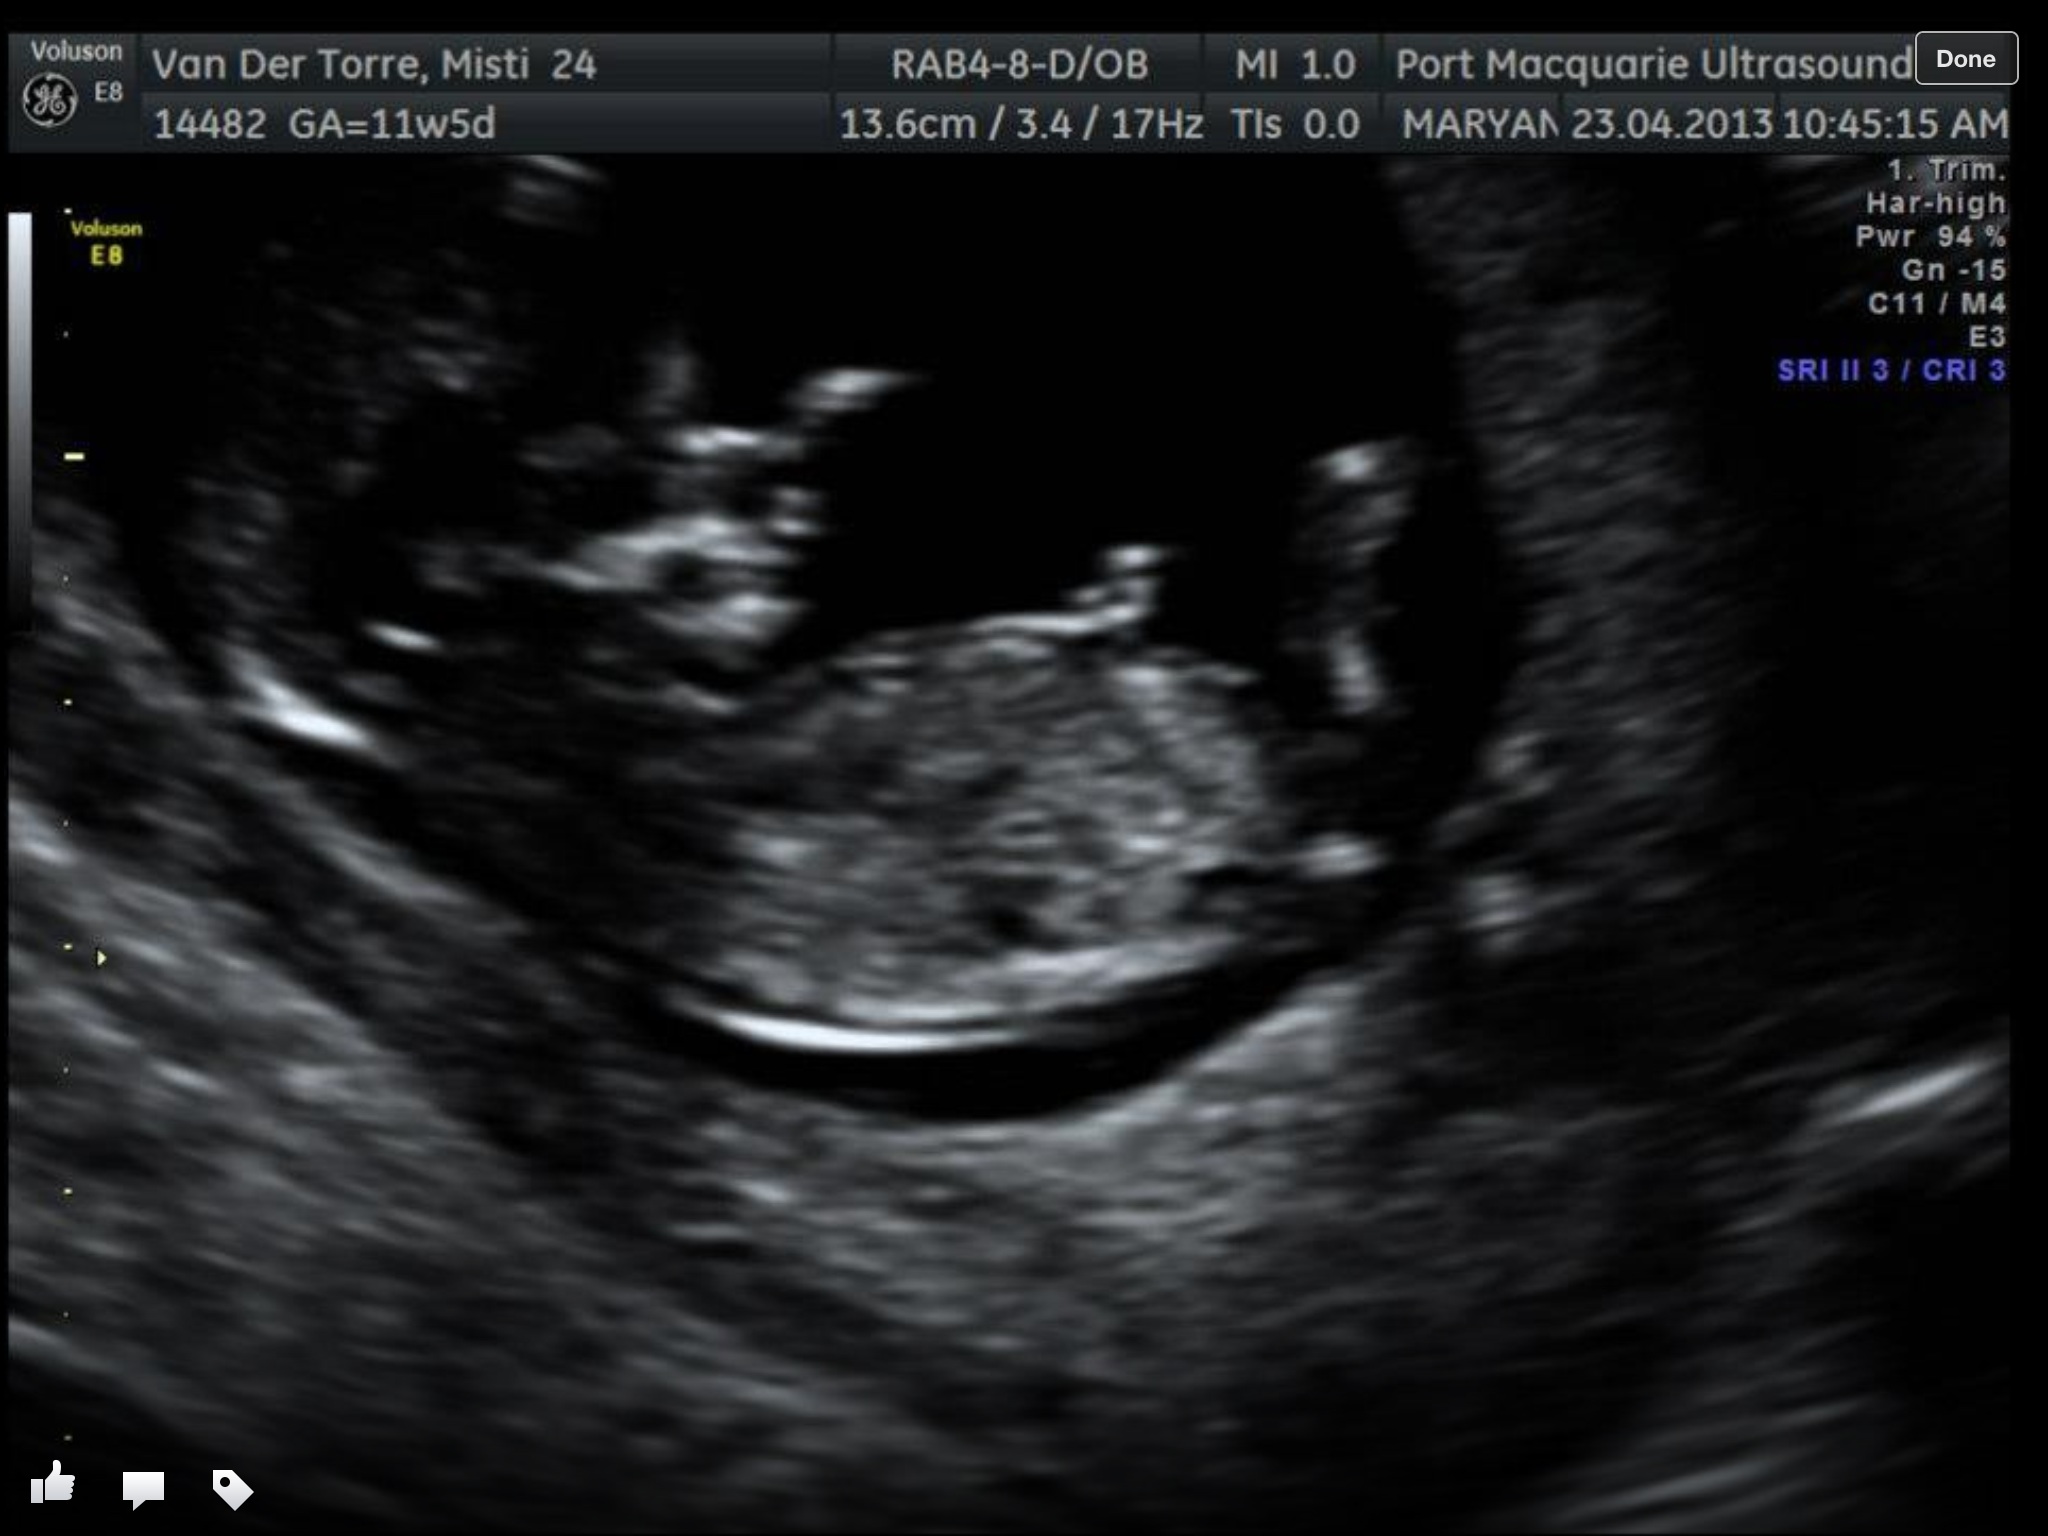

Hi all! I'm new here, just had my 12 week scan yesterday. I think I got 1 nub shot but there were 3 potentials. If anyone is willing to give their thoughts it would be greatly appreciated!